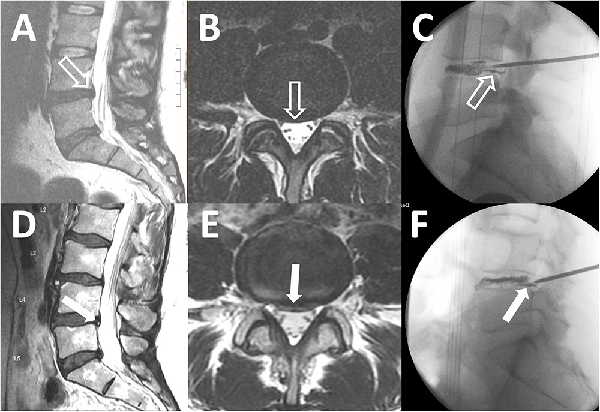

Figure 4

Subtle and obvious annular tears. T2 sagittal magnetic resonance imaging (MRI), T2 axial MRI, and the corresponding intraoperative discogram images show annular tears in patients with a subtle annular tear (A-C) and an obvious annular tear (D-F). A small bulging disc at L4-L5 without an associated high-intensity zone (HIZ) is indicated in panels A and B (open white arrows). Intraoperative discogram images reveal leakage of contrast through the annular tear (C, open white arrow). A bulging disc with an obvious HIZ is highlighted in panels D and E (solid white arrows). Intraoperative discogram images demonstrate leakage of contrast through the annular tear corresponding to the HIZ on MRI (F, solid white arrow). Note that there are also obvious annular tears at L5-S1 in panels A and D.

A third aspect of step B was for the spine surgeon to assess the lumbosacral MRI for the presence of a surgically treatable lumbosacral annular tear., All lumbosacral MRI had to have been of appropriate technical quality and performed within 12 months of clinical evaluation. The use of contrast material during the MRI procedure was not required unless there was previous lumbosacral spine surgery at the site of the annular tear. The following lumbosacral MRI categorization system was utilized. The patient was not considered a surgical candidate if there were no lumbosacral annular tears (Figure 3A) or if the patient had multilevel abnormalities where risks of surgery outweighed benefits (Figure 3B). The patient was a surgical candidate if the lumbosacral MRI revealed annular tears at 1, 2, or 3 spinal levels that could be treated by LESS. We then further classified the annular tear by severity per the following criteria: subtle if a disc bulge or protrusion was visualized but there was no accompanying high-intensity zone (Figure 4, A and B) and obvious if a high-intensity zone was visualized on the axial and sagittal T2-weighted images (Figure 4, D and E).

Patients with PGAD/GPD who met criteria for steps A to C in the management algorithm were considered candidates for endoscopic discectomy/annuloplasty with LESS. This technique is well described for the treatment of patients with back pain and radiculopathy.,, With a mixture of methylene blue and intravenous contrast media, a chromatodiscogram was performed to outline the annular defect (Figure 4, E and F). The annular defect on chromatodiscogram was identified in patients with subtle and obvious annular tears. The blue stain produced by the leakage of the methylene blue through the annular defect marked the pathologic area of the disc. Fragments of nucleus material trapped within the fissures of the posterior annulus were removed. Discrete tears and fissures in the annulus were ablated with the endoscopic radiofrequency probe (Trigger-Flex; Elliquence) and YAG-holmium probes (Lumenis). All patients were discharged the same day.

According to our criteria for severity, 10 patients were considered to have a subtle annular tear and 10 an obvious annular tear on lumbosacral MRI (Figure 4). As seen in Table 8, the most common locations were L4-L5 and L5-S1; 6 patients had annular tears at both these levels. These are common locations of lumbosacral spine injury, perhaps related to the transition zone between the flexible spine and the rigid sacrum., TFESI was performed in these patients, as determined by the multidisciplinary step-care management algorithm (Figure 1). All patients had a positive TFESI result, with a PGI-I score of 1, 2, or 3.